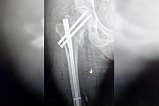

74-летняя пенсионерка поступила в травматологическое отделение Солнечногорской больницы с подозрением на перелом ноги. Специалисты в ходе обследования пожилой пациентки выявили у нее перелом бедренной кости со смещением.